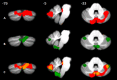

The literature on social cognition abilities in bipolar disorder (BD) is controversial about the occurrence of theory of mind (ToM) alterations. In addition to other cerebral structures, such as the frontal and limbic areas, the processing of socially relevant stimuli has also been attributed to the cerebellum, which has been demonstrated to be involved in the above-mentioned disorder. Nevertheless, the cerebellar contribution to ToM deficits in bipolar patients needs to be elucidated further. To this aim, two tests assessing different components of ToM were used to evaluate the ability to appreciate affective and mental states of others in 17 individuals with a diagnosis of BD type 1 (BD1) and 13 with BD type 2 (BD2), both in the euthymic phase, compared to healthy matched controls. Cerebellar gray matter (GM) volumes were extracted and compared between BD1 and controls and BD2 and controls by using voxel-based morphometry. The results showed that BD1 patients were compromised in the cognitive and advanced components of ToM, while the BD2 ToM profile resulted in a more widespread compromise, also involving affective and automatic components. Both overlapping and differing areas of cerebellar GM reduction were found. The two groups of patients presented a pattern of GM reduction in cerebellar portions that are known to be involved in the affective and social domains, such as the vermis and Crus I and Crus II. Interestingly, in both BD1 and BD2, positive correlations were detected between lower ToM scores and decreased volumes in the cerebellum. Overall, BD2 patients showed a more compromised ToM profile and greater cerebellar impairment than BD1 patients. The different patterns of structural abnormalities may account for the different ToM performances evidenced, thus leading to divergent profiles between BD1 and BD2.